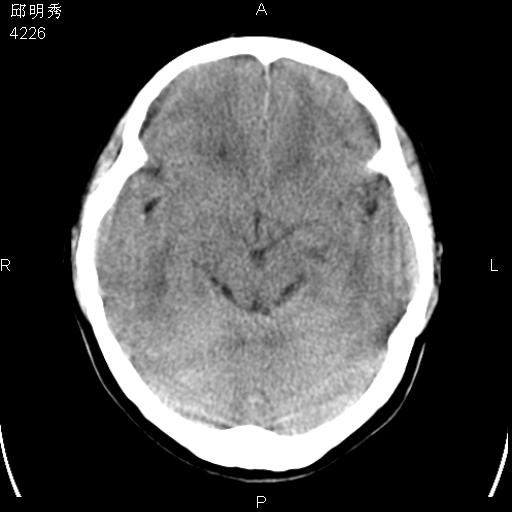

40f头晕十多天,右上肢麻木一天

脑白质变性或ms

脑白质脱髓鞘改变。

脑白质病;建议行mri检查。